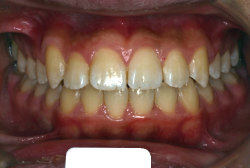

過蓋咬合

過蓋(かがい)咬合とは、奥歯を閉じた時に前歯が深く咬み込み、下の前歯がほとんど見えなくなるくらい閉じすぎになる症状です。強く咬んでいると言うことは、力が強く出て一見良さそうに聞こえますが、深く咬みすぎることは歯にも良くないですし、口腔周囲の環境としても好ましくない状態です。

「歯並びの凸凹を直したい」という主訴で来院したケースです。診断の結果、たしかに「叢生」という隙間が足りないと言うことが原因の凸凹症例でした。

しかし、それ以上に問題なのは「前歯の噛み合い方が深すぎる」という症状で、初診の歯の正面写真を見ると下の前歯が全く見えません。こういう症状を矯正学では「過蓋咬合(かがいこうごう)」と言います。過蓋咬合を放置すると、将来的に顎関節に悪影響を与えるとされており、顎関節症の原因因子の一つです。また下の前歯の先端が、上の前歯の裏側の歯茎と強く接触するため、歯周病の原因にもなります。

検査の結果、凸凹が軽症なため非抜歯で矯正すること可能と判断、マルチブラケット装置にて治療しました。治療後は歯並びが綺麗になっただけでなく、噛み合わせ的にも正しい状態が確立しています。